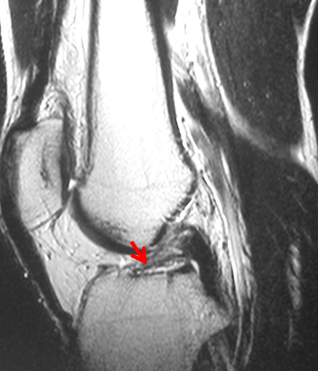

MRI

正常前交叉韧带

前交叉韧带损伤后形成的疤痕组织